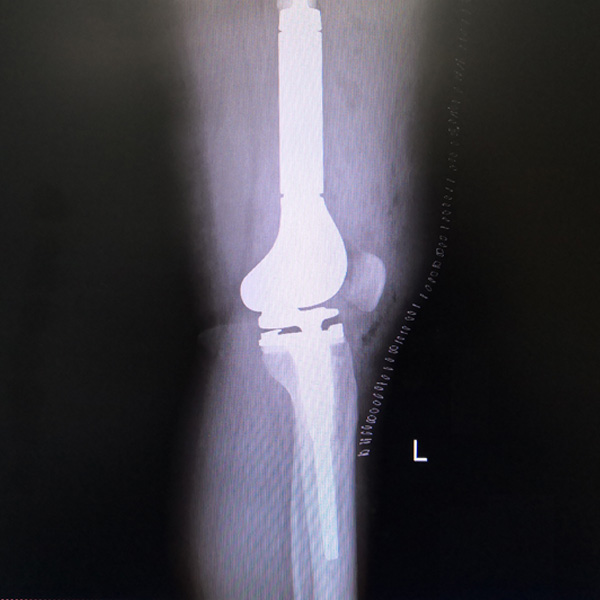

膝關(guān)節(jié)內(nèi)翻

患者劉某某,女66歲,左側(cè)膝關(guān)節(jié)嚴(yán)重內(nèi)翻(俗稱(chēng)的“羅圈腿”),疼痛到不能生活自理。經(jīng)平臺(tái)推薦到哈爾濱醫(yī)科大學(xué)附屬第二醫(yī)院骨關(guān)節(jié)科就診,......